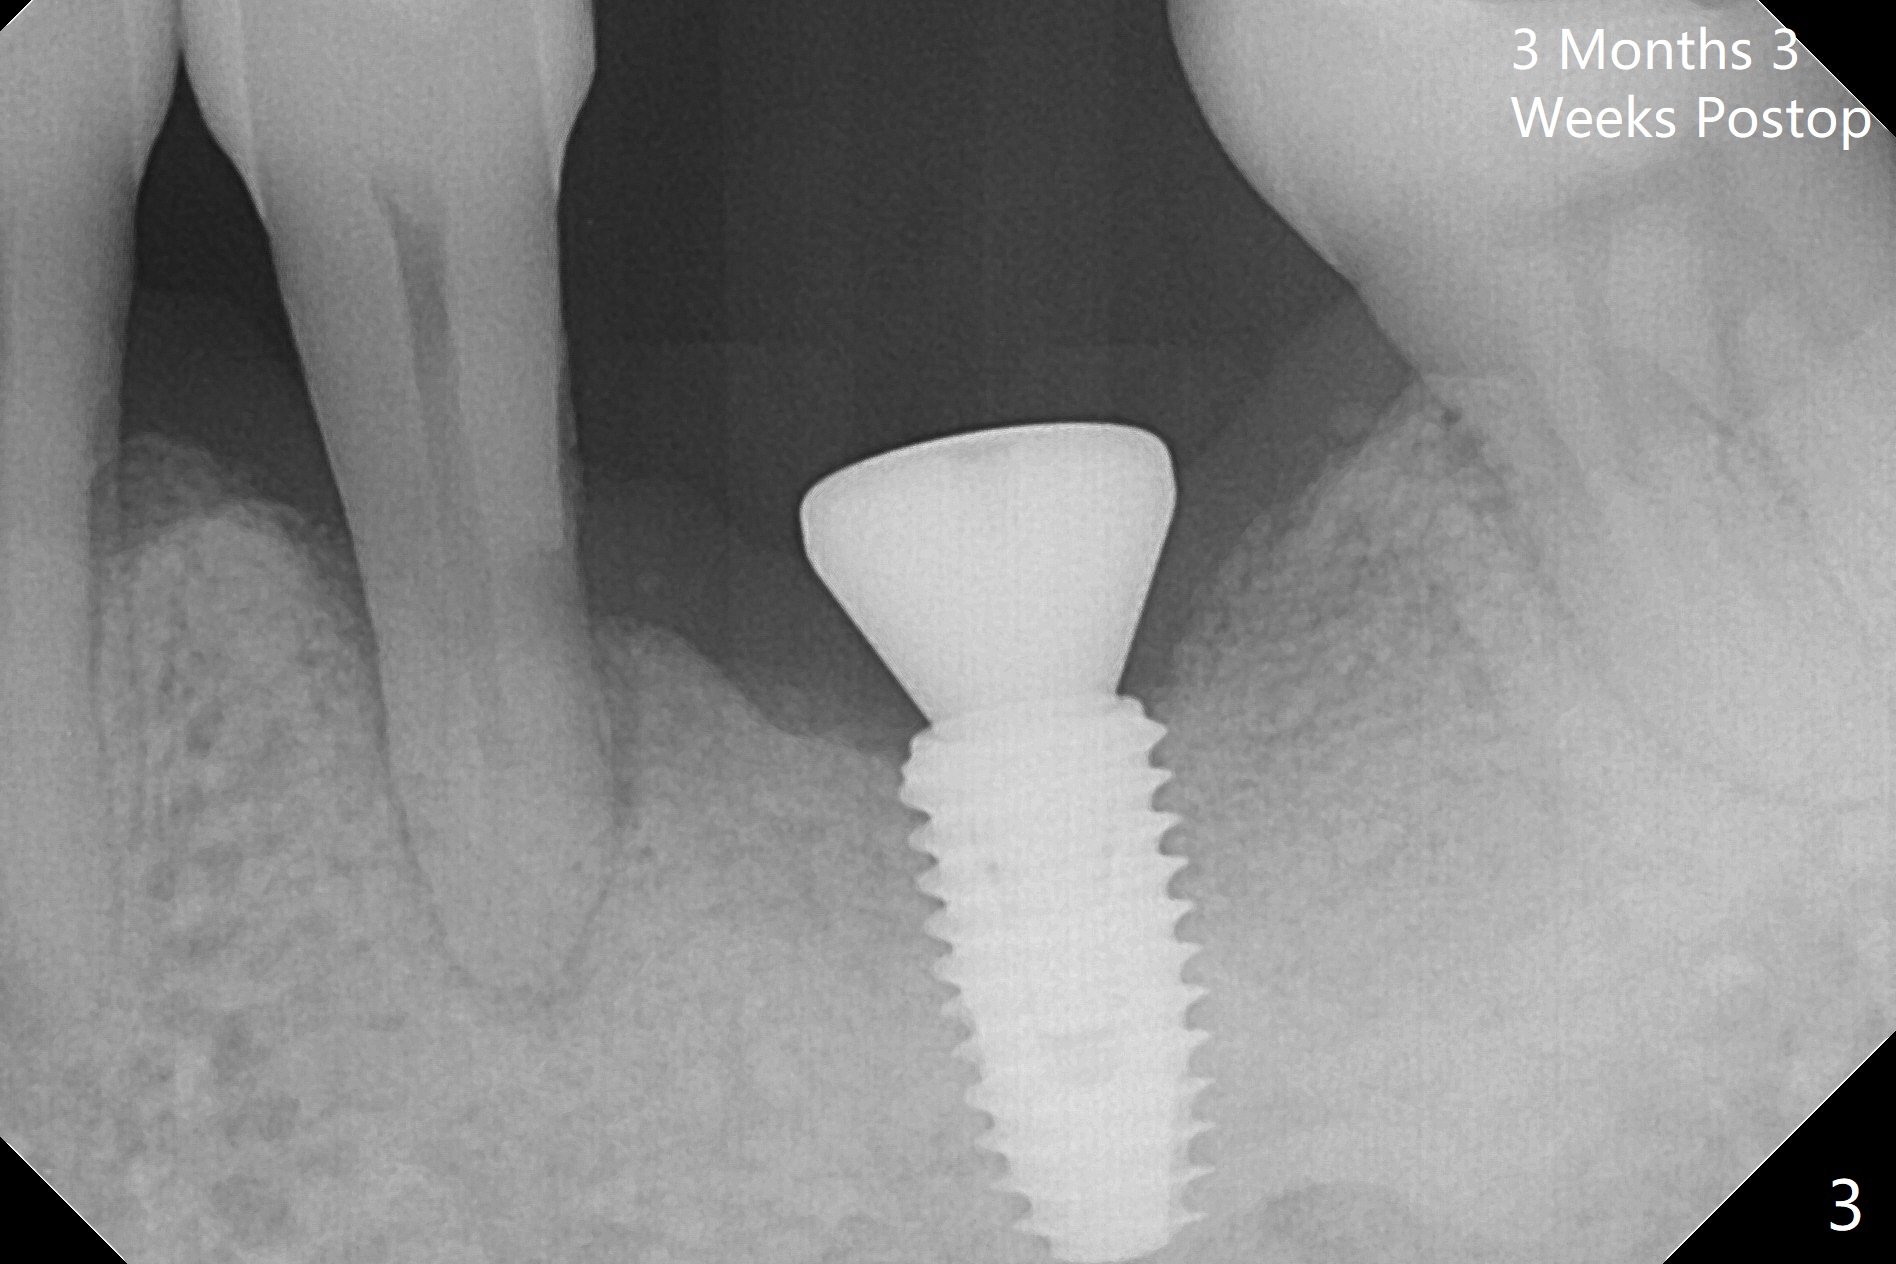

In fact the patient returns for impression 3 months 23 days postop; there is no bone loss at the crestal level (Fig.3). The patient returns 7 months post cementation. The access hole composite dislodges, but the abutment screw is tight, which is associated with the correct trajectory and guide. The crestal bone contacts the implant plateau 11 months post cementation (Fig.4 arrowheads).